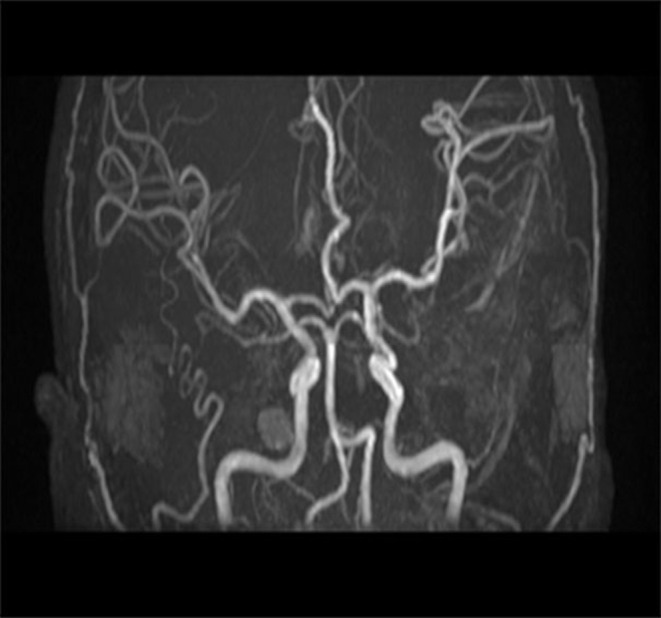

Methods and patient presentation: We report an 18-year-old student of EGPA complicated with intracerebral hemorrhage. The laboratory tests showed a continuous increase in eosinophils. The CT of head and chest showed cerebral hemorrhage and pulmonary infiltration.

Outcomes: At discharge, the patient's head and chest CT showed obvious absorption of intracranial hematoma and improvement of pulmonary infiltration. We reviewed 40 previously published cases of EGPA with intracerebral hemorrhage focusing on the clinical features and treatment of intracerebral hemorrhage caused by EGPA.